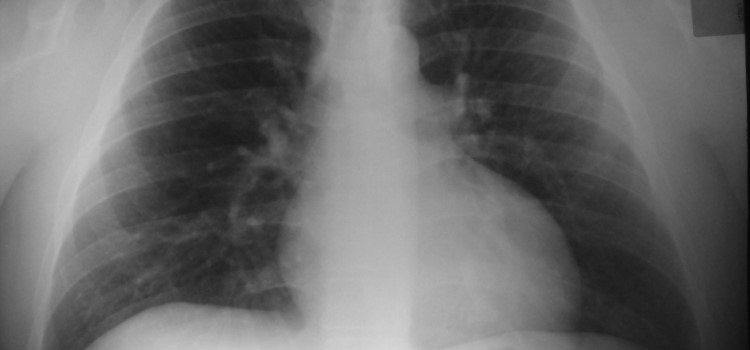

Radiografía de los contagios de coronavirus: el 40% tiene menos de 40 años y la mayoría no sabe dónde se ha infectado 23.07.2020 Uno de cada cuatro se contagió en el domicilio, pero en un 37% de casos se desconoce dónde pudo exponerse